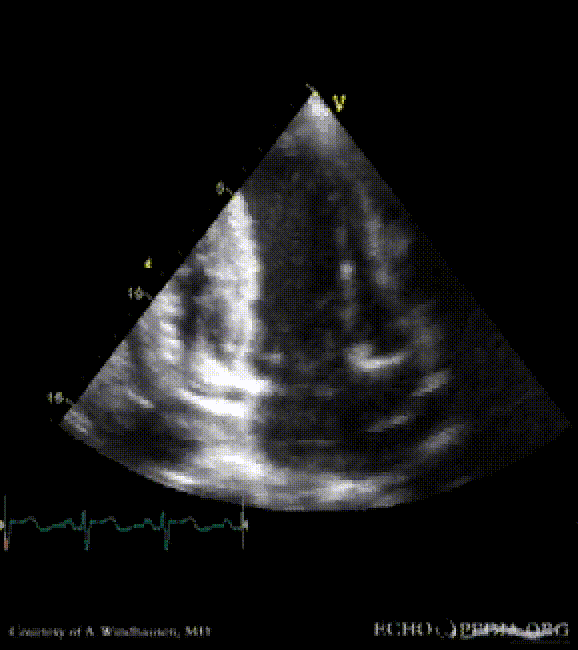

Severe Hypertrophic Cardiomyopathy (HCM)

Case description: Severe Hypertrophic Cardiomyopathy (HCM)

Courtesy of: A. Windhausen, AMC, The Netherlands

MM0001.gif MM0002.gif

A2CH view A4CH view